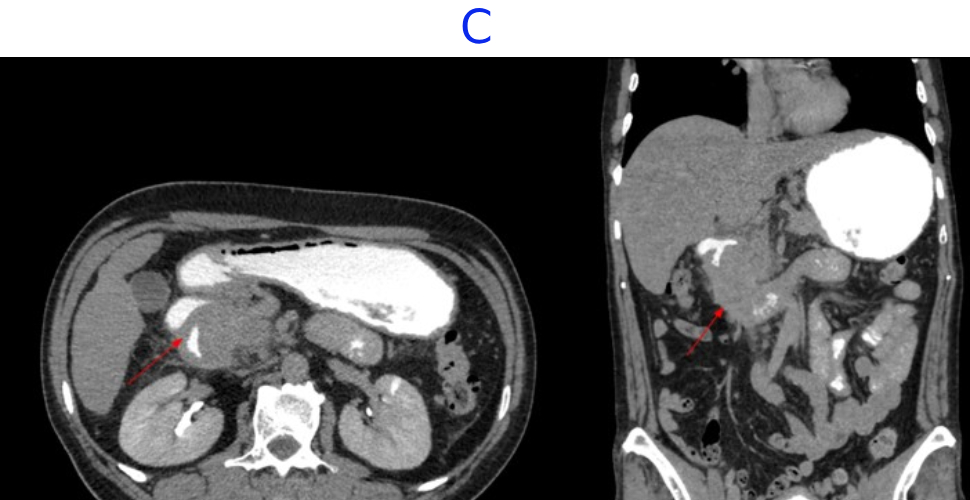

- C. Contrast is seen passing from the duodenum into the jejunum. No contrast leakage noted.